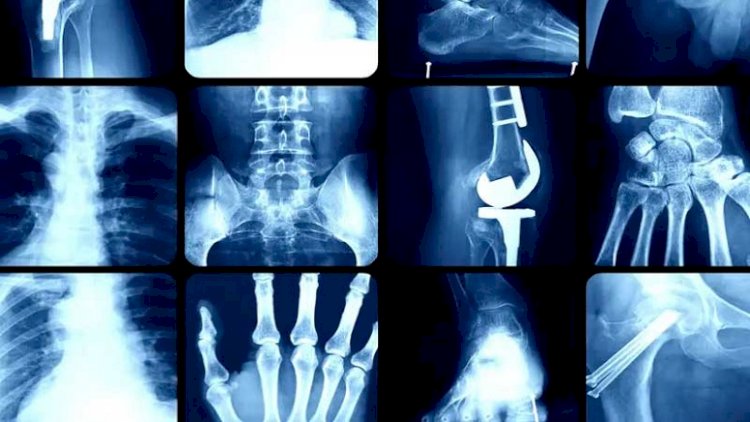

অস্টিওপোরোসিস বলতে হাড়ের ঘনত্ব কমে যাওয়াকে বোঝায়। হাড়ক্ষয়ের এ সমস্যায় সামান্য আঘাতেই হাড় ভেঙে যেতে পারে। সমস্যা মারাত্মক হলে হাঁচি বা কাশি দিলেও হাড় ভেঙে যেতে পারে। বয়স্ক নারীদের বিকলাঙ্গ বা মৃত্যুর অন্যতম কারণ এটি। বয়স ৫০ বছর পার হওয়ার পর হাড়ক্ষয়ের ঝুঁকি বেড়ে যায়। তবে এ সমস্যার সূত্রপাত হতে পারে আরও আগেই। নারীদের মেনোপজ বা মাসিক বন্ধ হয়ে যাওয়ার পরবর্তী সময়ে হাড়ক্ষয়ের ঝুঁকি আরও বেড়ে যায়। এ ছাড়া অনেক কারণে হাড়ক্ষয়ের আশঙ্কা তৈরি হতে পারে। এর মধ্যে সংশোধনযোগ্য ঝুঁকিগুলো হলো-

আবার কিছু ঝুঁকি আছে অসংশোধনযোগ্য, মানে চাইলেও এড়ানো যায় না। যেমন- বয়স, জিনগত ত্রুটি, অস্ত্রোপচার করে জরায়ু ফেলে দিলে, সময়ের আগে মেনোপজ, রক্তে সেক্স হরমোনের ঘাটতি, অতি খর্বাকৃতি ইত্যাদি। দীর্ঘদিন শয্যাশায়ী থাকা, স্টেরয়েড জাতীয় ওষুধ সেবন, হরমোনজনিত রোগ যেমন হাইপারথাইরয়েডিজম, অ্যাড্রিনাল গ্রন্থির সমস্যা, রিউমাটয়েড আর্থ্রাইটিসের মতো কিছু বাতরোগ, কিডনি অকার্যকর হলে অস্টিওপোরোসিসের ঝুঁকি বাড়ে।

প্রাথমিক অবস্থায় হাড়ক্ষয়ের তেমন উপসর্গ থাকে না। বয়স্ক নারীদের কোমরে বা পিঠে ব্যথা না কমলে মেরুদণ্ডের হাড়ে ফাটল দেখা দিয়েছে কিনা দেখতে হবে। কুঁজো হয়ে যাওয়া, সামনে ঝুঁকে দাঁড়ানো বা হাঁটা এ সমস্যার লক্ষণ। রোগীর ব্যক্তিগত ইতিহাস, উপসর্গ মিলিয়ে চিকিৎসক ঝুঁকি নির্ণয় করতে পারেন।